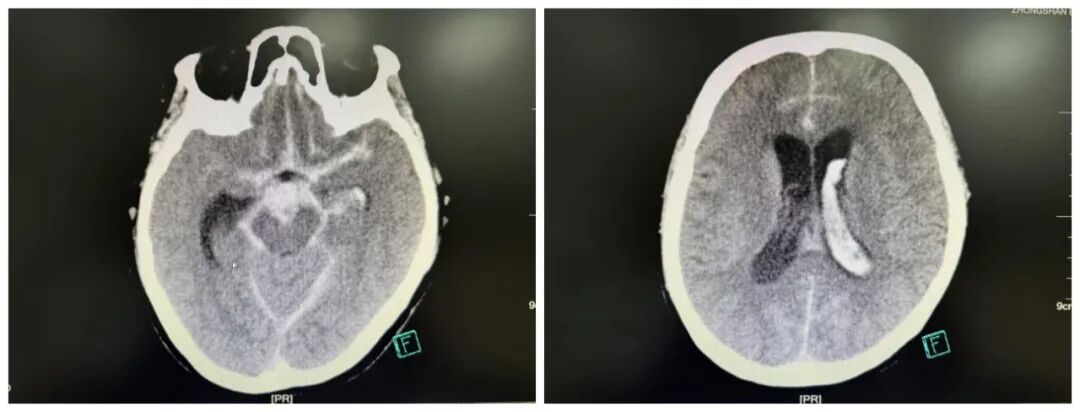

脑子里“炸”了?64岁阿姨突发爆炸性头痛……

与时间赛跑

2025年8月,64 岁的陈姨(化名)突发剧烈头痛,随后陷入昏迷,家人紧急将其送往中山市博爱医院,距发病已过去2小时。急诊头部CT检查显示,她颅内有大量蛛网膜下腔出血,且已破入脑室——这正是脑动脉瘤破裂的典型表现,病死率和致残率极高。血管内介入治疗是此类急症的主要救治手段,中山市博爱医院神经外科团队以及介入科迅速响应,精准植入Web扰流装置封堵动脉瘤,随后为其实施脑室外引流术,如今陈姨恢复良好,未留下神经功能障碍。

(通过介入手术植入Web扰流装置)